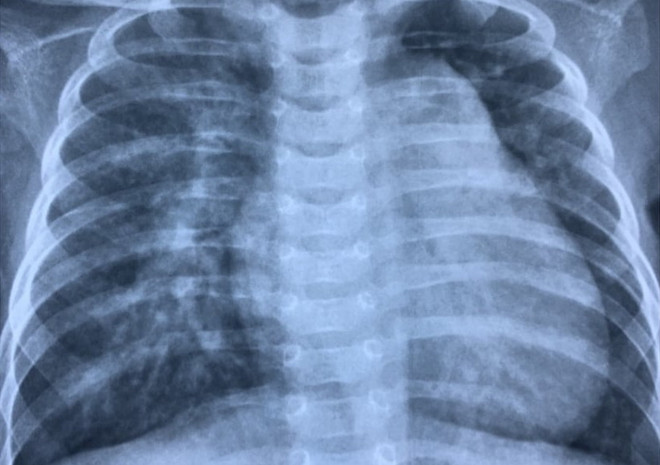

Ứng dụng thành công kỹ thuật Hybrid cho ca bệnh nhỏ tuổi nhất Việt Nam ảnh 1Phim chụp ngực bệnh nhi trước can thiệp. (Ảnh: PV/Vietnam+)